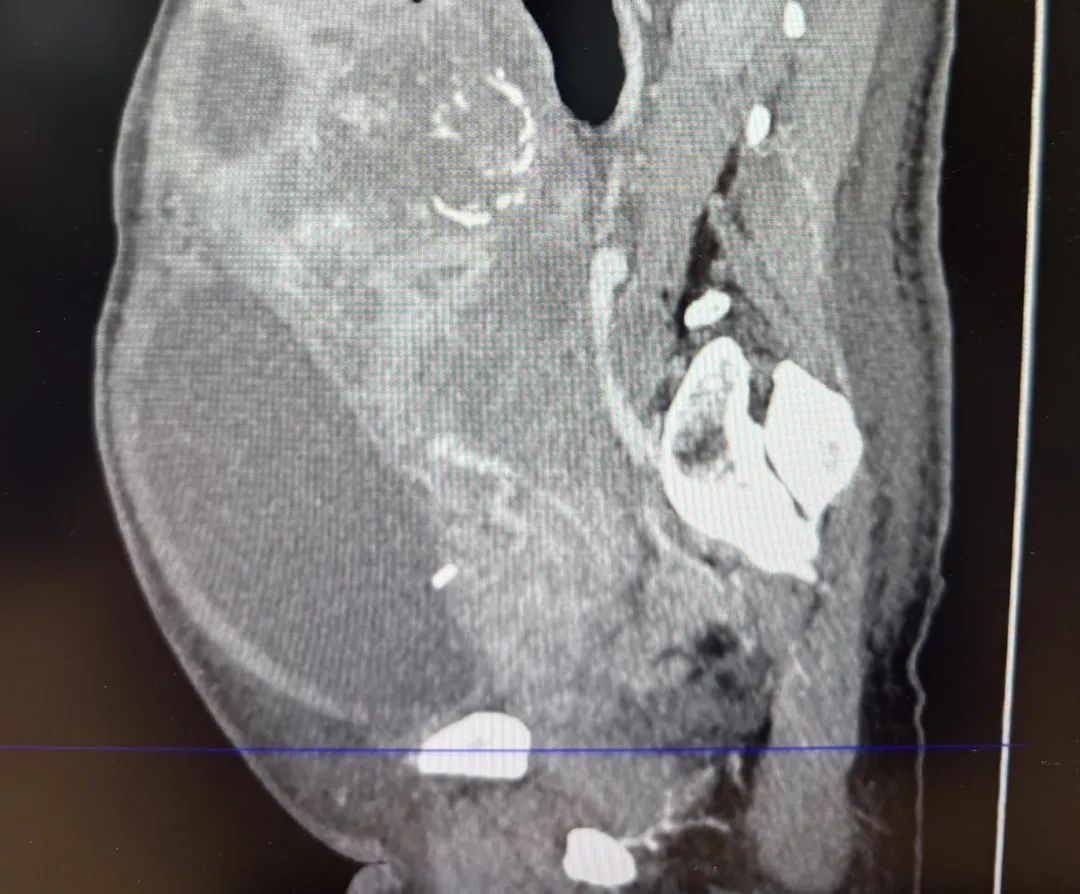

门诊就诊的章女士及术前影像检查

然而,最让李华主任担忧的是,肿物上达肋缘、下达近外阴,坚如磐石,且外院穿刺的肿瘤病理类型为子宫癌肉瘤,这类肿瘤血供极其丰富,出血风险巨大。因此,如此巨大的肿物一旦手术,术中操作空间将十分受限,止血将非常困难,手术过程中可能瞬间出血几千毫升,随时危及生命。